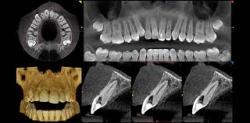

Dental cone beam computed tomography (CT) is a special type of x-ray machine used in situations where regular dental or facial x-rays are not sufficient. It is not used routinely because the radiation exposure from this scanner is significantly more than regular dental x-rays. See the Safety page for more information about x-rays. This type of CT scanner uses a special type of technology to generate three dimensional (3-D) images of dental structures, soft tissues, nerve paths and bone in the craniofacial region in a single scan. Images obtained with cone beam CT allow for more precise treatment planning.

With cone beam CT, an x-ray beam in the shape of a cone is moved around the patient to produce a large number of images, also called views. CT scans and cone beam CT both produce high-quality images.

Cone beam CT provides detailed images of the bone and is performed to evaluate diseases of the jaw, dentition, bony structures of the face, nasal cavity and sinuses. It does not provide the full diagnostic information available with conventional CT, particularly in evaluation of soft tissue structures such as muscles, lymph nodes, glands and nerves. However, cone beam CT has the advantage of lower radiation exposure compared to conventional CT.

The x-ray source and detector are mounted on opposite sides of the revolving C-arm or gantry and rotate in unison. In a single rotation, the detector can generate anywhere between 150 to 200 high resolution two-dimensional (2-D) images, which are then digitally combined to form a 3-D image that can provide your dentist or oral surgeon with valuable information about your oral and craniofacial health.